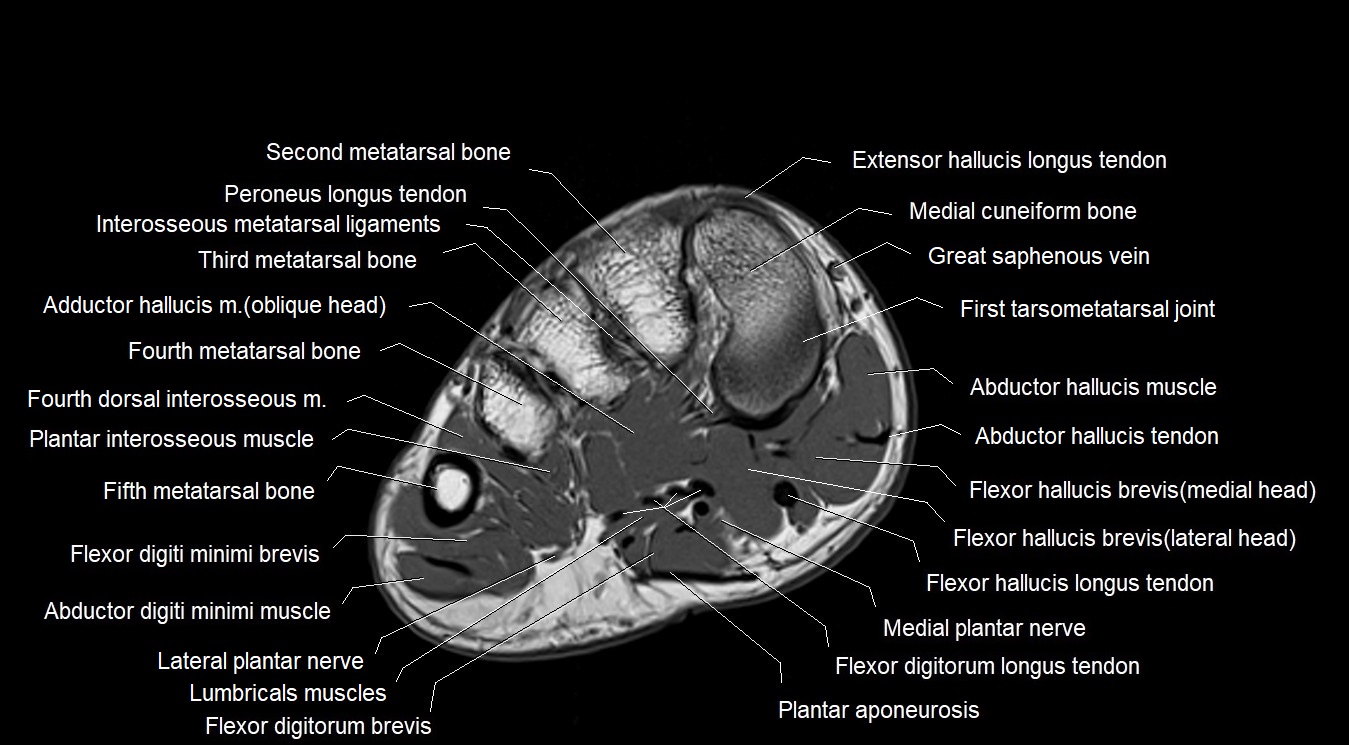

MRI image